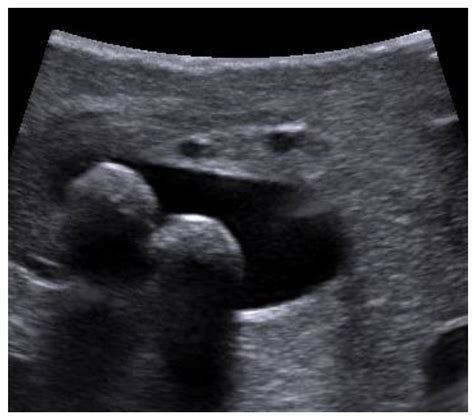

The diagnostic power of Choledocholithiasis On Ultrasound primarily relies on identifying:

• Dilation of the Common Bile Duct (CBD): A duct measuring over 6–7 mm is often considered dilated, suggesting a potential obstruction.

• Direct Visualization of Stones: While challenging due to bowel gas, high-frequency transducers can sometimes visualize echogenic foci with acoustic shadowing within the duct.

• Secondary Indicators: Findings such as gallbladder sludge or multiple stones within the gallbladder increase the clinical suspicion that a stone has migrated into the duct.